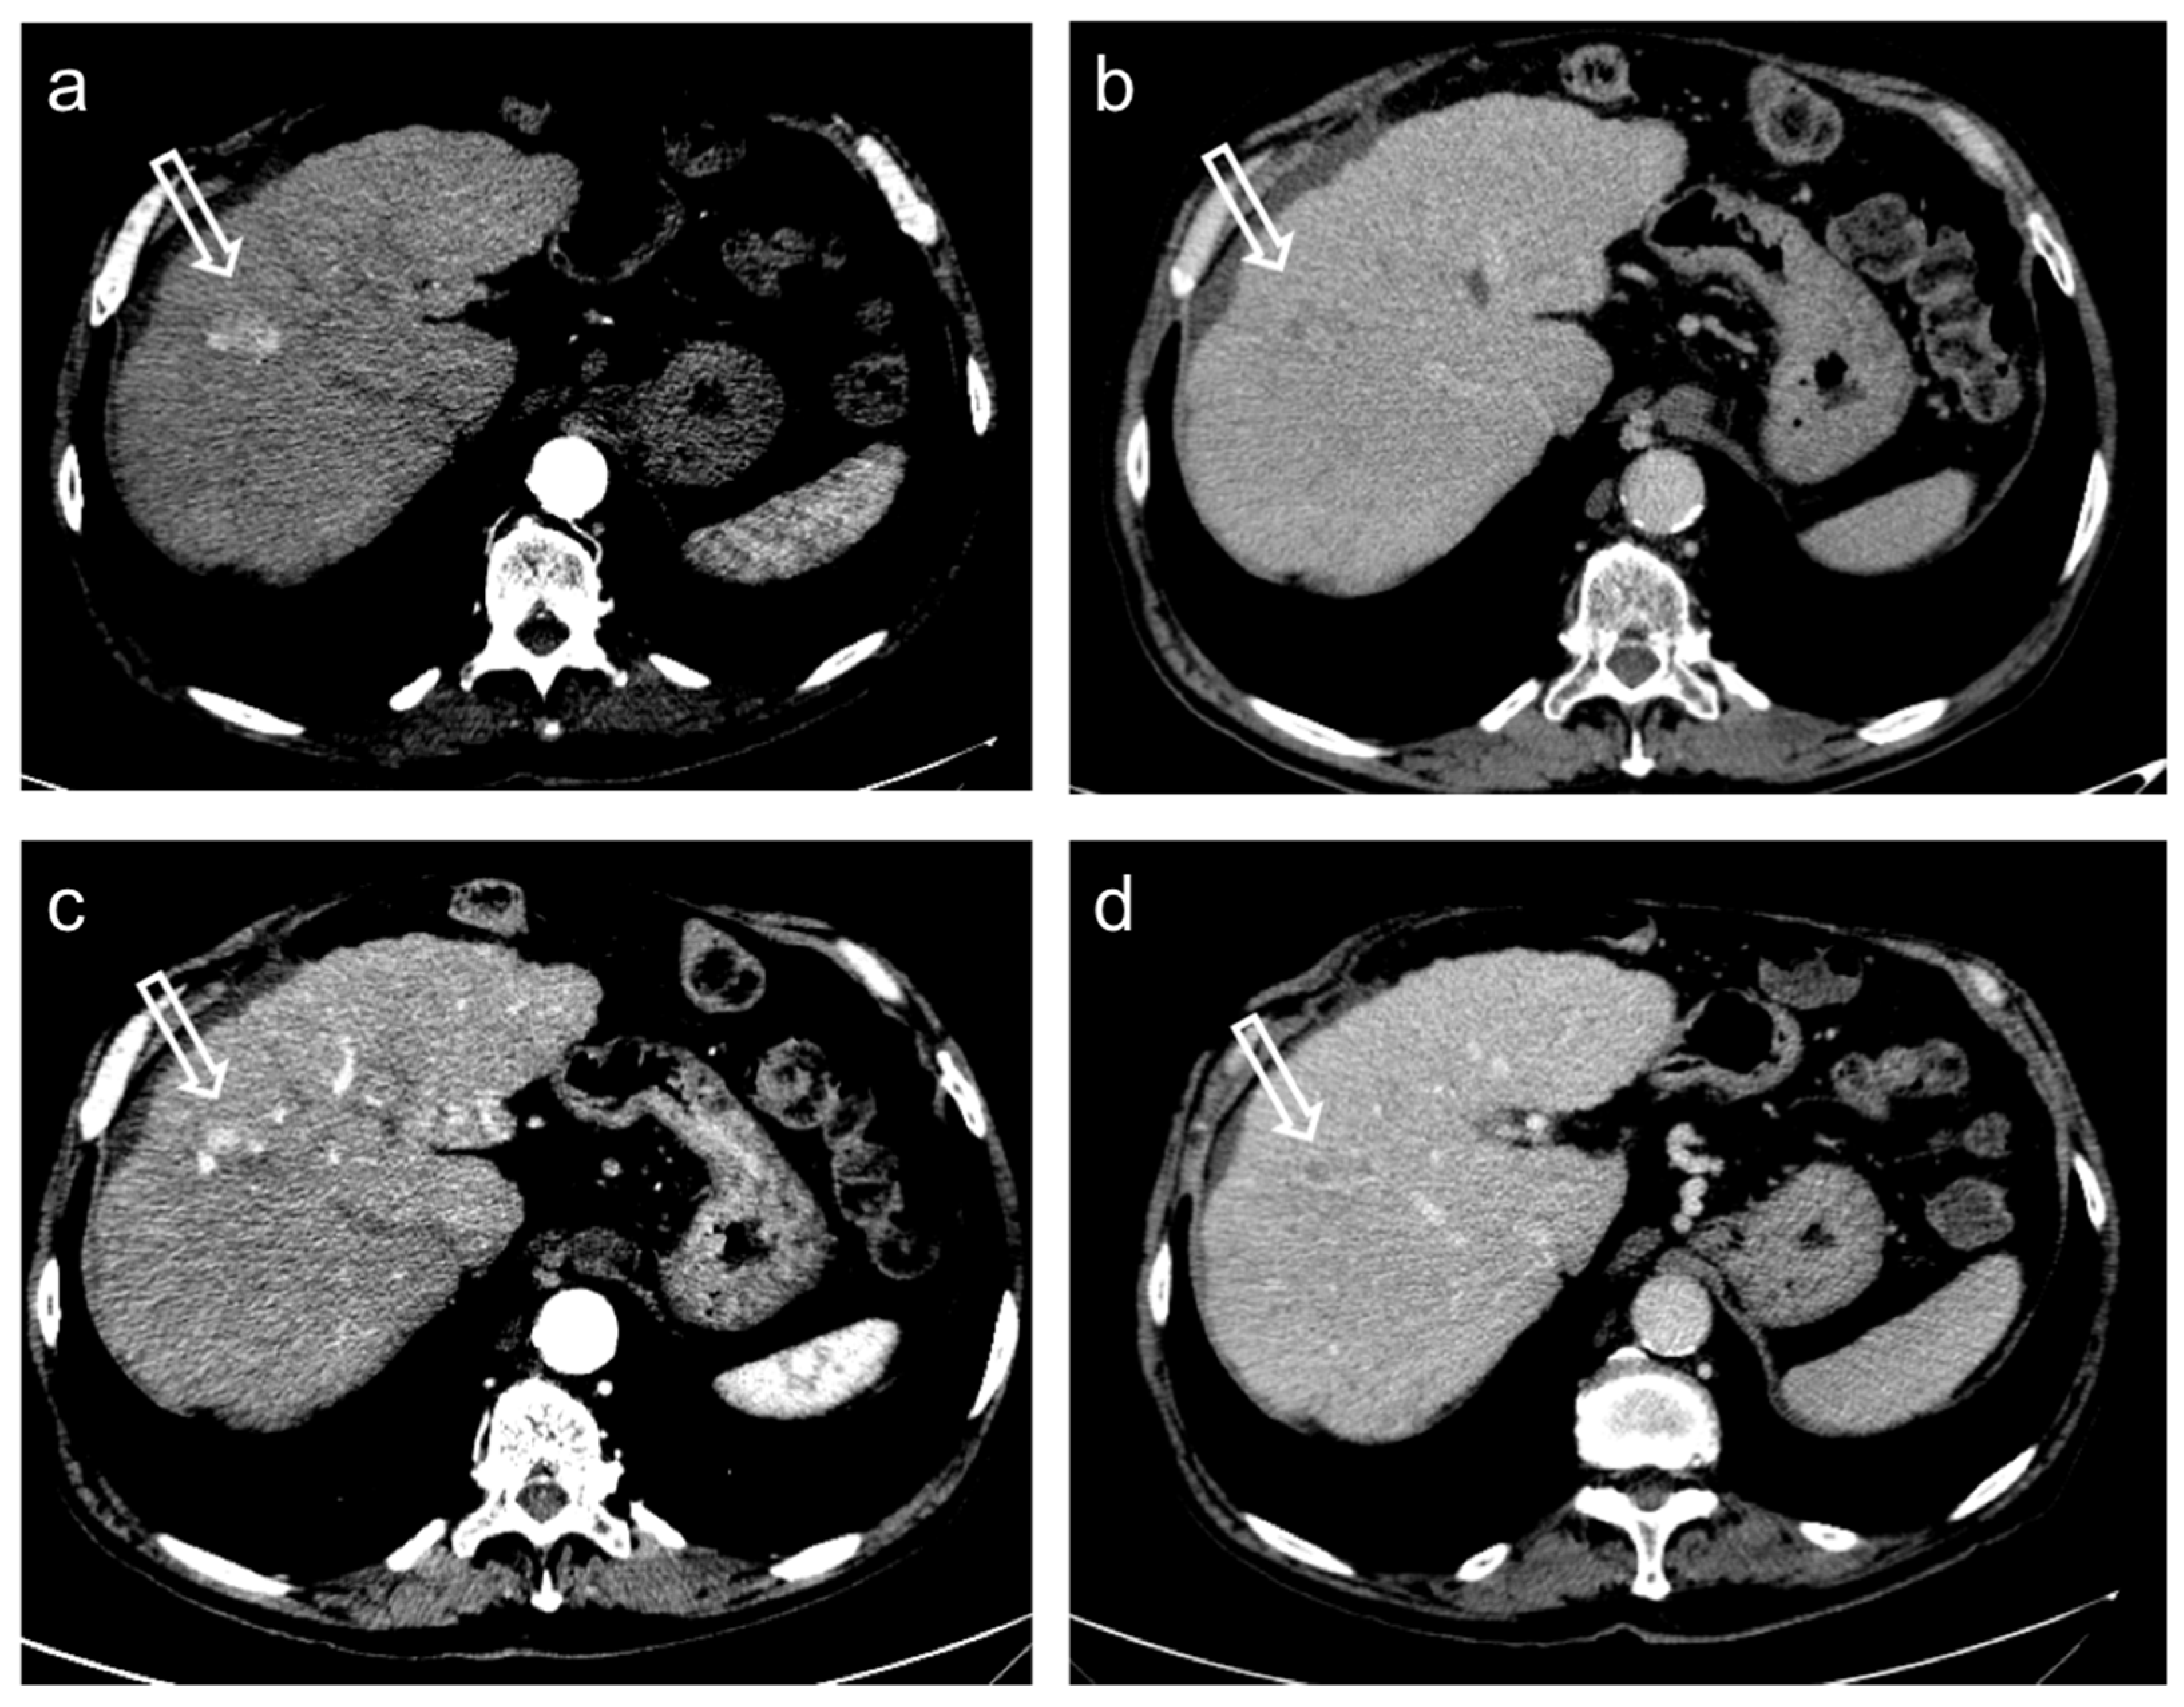

3. Treatment Response Criteria